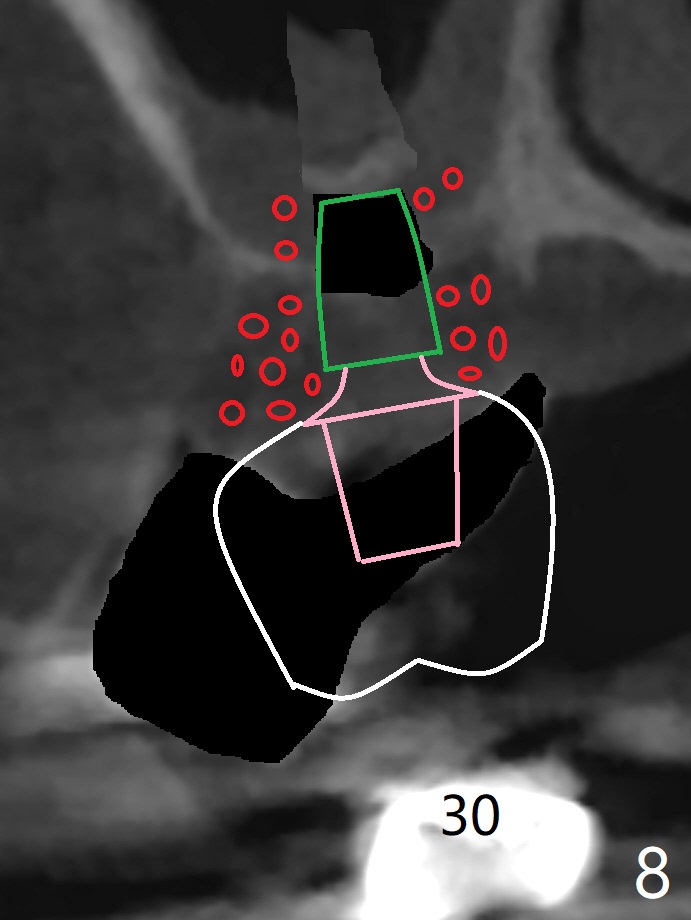

A 51-year-old woman has poor dentition with chronic periodontitis (Fig.1). She has financial constraint, but refuses RPD, insisting upon UR posterior implants first. After discussion of severe bone loss, she agrees with bone graft first (Fig.2-4). Since the bone atrophy is the most severe at #3 (Fig.5 coronal section; L: lingual), sinus lift (Fig.6 arrow) is conducted after extraction (black). Use sticky bone (Fig.7 red circles) and Titanium-reinforced Cytoplast (white) for socket preservation. Or if Magicore is able to achieve primary stability (Fig.8 green), an abutment (pink) will be placed for an immediate provisional (white). The latter are capable of holding bone graft in place. Since bone loss at #2 and 4 is less severe (Fig.9 sagittal section), their roots will act as walls to keep bone graft (Fig.11) in place after #3 extraction (Fig.10).